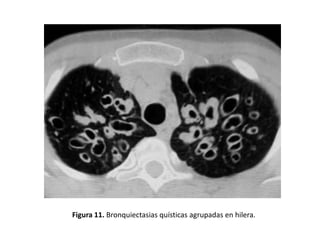

• Pueden verse imágenes aéreas con pared definida o

lesiones quísticas, con o sin nivel hidroaéreo (Figura

11)

Figura 11. Bronquiectasias quísticas agrupadas en hilera.

• Quísticas:

– Es la expresión más grave de la enfermedad.

– Los bronquios adquieren una forma sacular o de

quiste.

– Pueden presentar niveles hidroaéreos o estar

agrupadas en racimos o hileras.

– Adoptan la típica imagen de “nido de golondrina”

cuando el moco se acumula dentro de las lesiones y

aparece un nivel hidroaéreo (Figuras 11, 14, 15, 17, 21

y 25).

– Son frecuentes en la aspergilosis broncopulmonar

alérgica (ABPA) y en la fibrosis quística